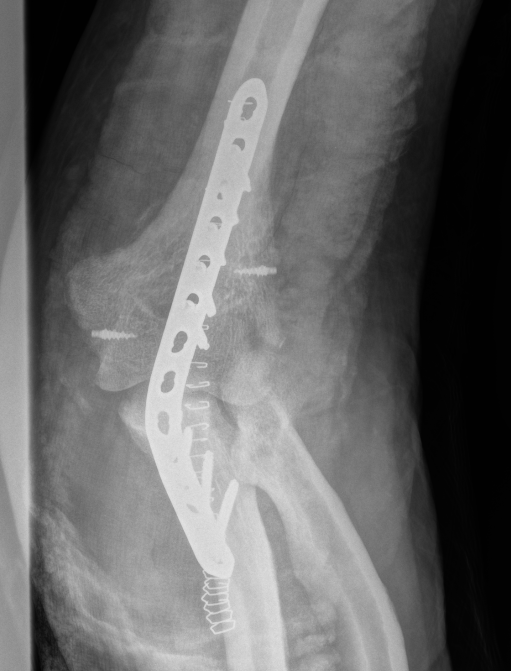

Internal fixation with posterior plating

Surgical technique